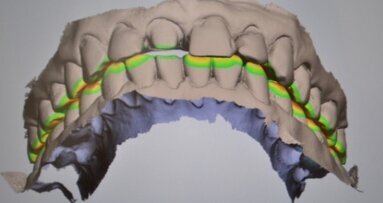

Kolejnym etapem jest zarejestrowanie okluzji. W tym celu prosimy pacjenta o zagryzienie zębów i skanujemy grupę 2-3 zębów dolnych wraz z przylegającym do nich dziąsłem oraz grupę 2-3 zębów przeciwstawnych(górnych), także z przylegającym dziąsłem.Skaner automatycznie składa zeskanowane wcześniej łuki górny i dolny w prawidłowym okluzyjnym położeniu (Ryc. 6).

Jeszcze jedna ważna cecha skanera wewnątrzustnego ułatwiająca bezpośrednią diagnostykę to analiza odległości łuków zębowych względem siebie, a szczególnie odległości oszlifowanego zęba od zęba przeciwstawnego. Do określenia tych wartości służy skalibrowana mapa kolorów (Ryc. 24-26).